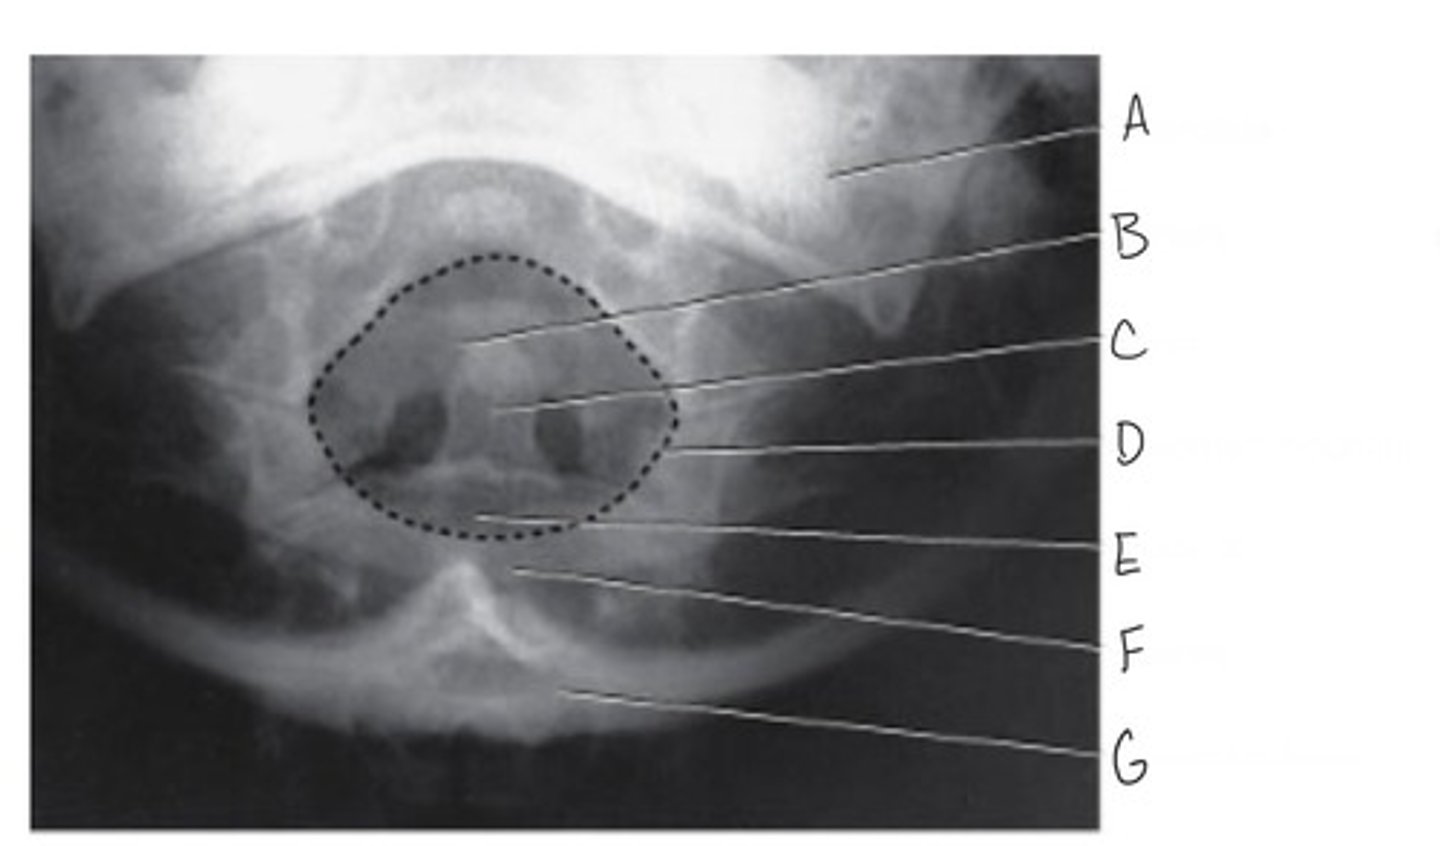

AP (open mouth) of the cervical spine: Atlas & Axis

What projection is this?

Occipital base

What is A?

Occlusal surface of teeth

What is B?

Den (odontoid process)

What is C?

Mandibular ramus

What is D?

Lateral mass of atlas

What is E?

Inferior articular process of atlas

What is F?

Spinous process of axis

What is G?